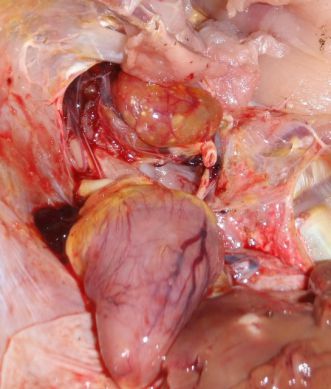

تخم نطفه دار - مرغ گوشتیدستگاه جوجه کشی - گرفتگی عروق قلب طیور ناشی از آسیتماشین جوجه درآوری - بررسی علائم آسیت در لاشه طیور

آسیت در واقع تجمع مایعی سرشار از پروتئین در حفره های بدنی است. به دلیل سطح پروتئین بالا ممکن است توده هایی از یک ماده زرد ژله مانند در بدن تشکیل گردد

در پرندگان سمت راست قلب دارای دیواره ای نازک بوده و دریچه موجود در این ناحیه به دیواره قلب ضربه می زند. همچنین شش های پرندگان با سایر جانداران متفاوت می باشد، به نحوی که دارای توانایی خیلی کمی جهت انبساط بوده و مویرگ های شش ها توانایی کنترل و تحمل مقادیر بالای جریان یا فشار خون را ندارند

زمانیکه سمت راست قلب با فشار خون بالا در عروق خونی مواجه می گردد، حجم کار آن مانند سایر ماهیچه ها بالا می رود که این پدیده در واقع با بزرگتر شدن صورت می پذیرد. اگر فشار همچنان بالا باقی بماند، ماهیچه ها همچنان به ضخیم شدن ادامه می دهند تا زمانیکه دریچه دیگر قادر به بسته شدن به طور کامل نخواهد بود

تشخیص

پرندگانی

که از آسیت می میرند بسیار ساده است. کافی است هنگام کالبد شکافی کمر پرنده باز شود در اینصورت مقدار قابل توجهی ماده خونی و یا ژله مانند از آن بیرون می ریزد گاهی اوقات پرندگان مبتلا به آسیت به دلیل اثرات ناشی از وجود مقادیر بسیار زیاد خون و جریان در شش هایشان می میرند قبل از اینکه مقدار قابل توجهی از جریان در حفره های بدن تشکیل شود